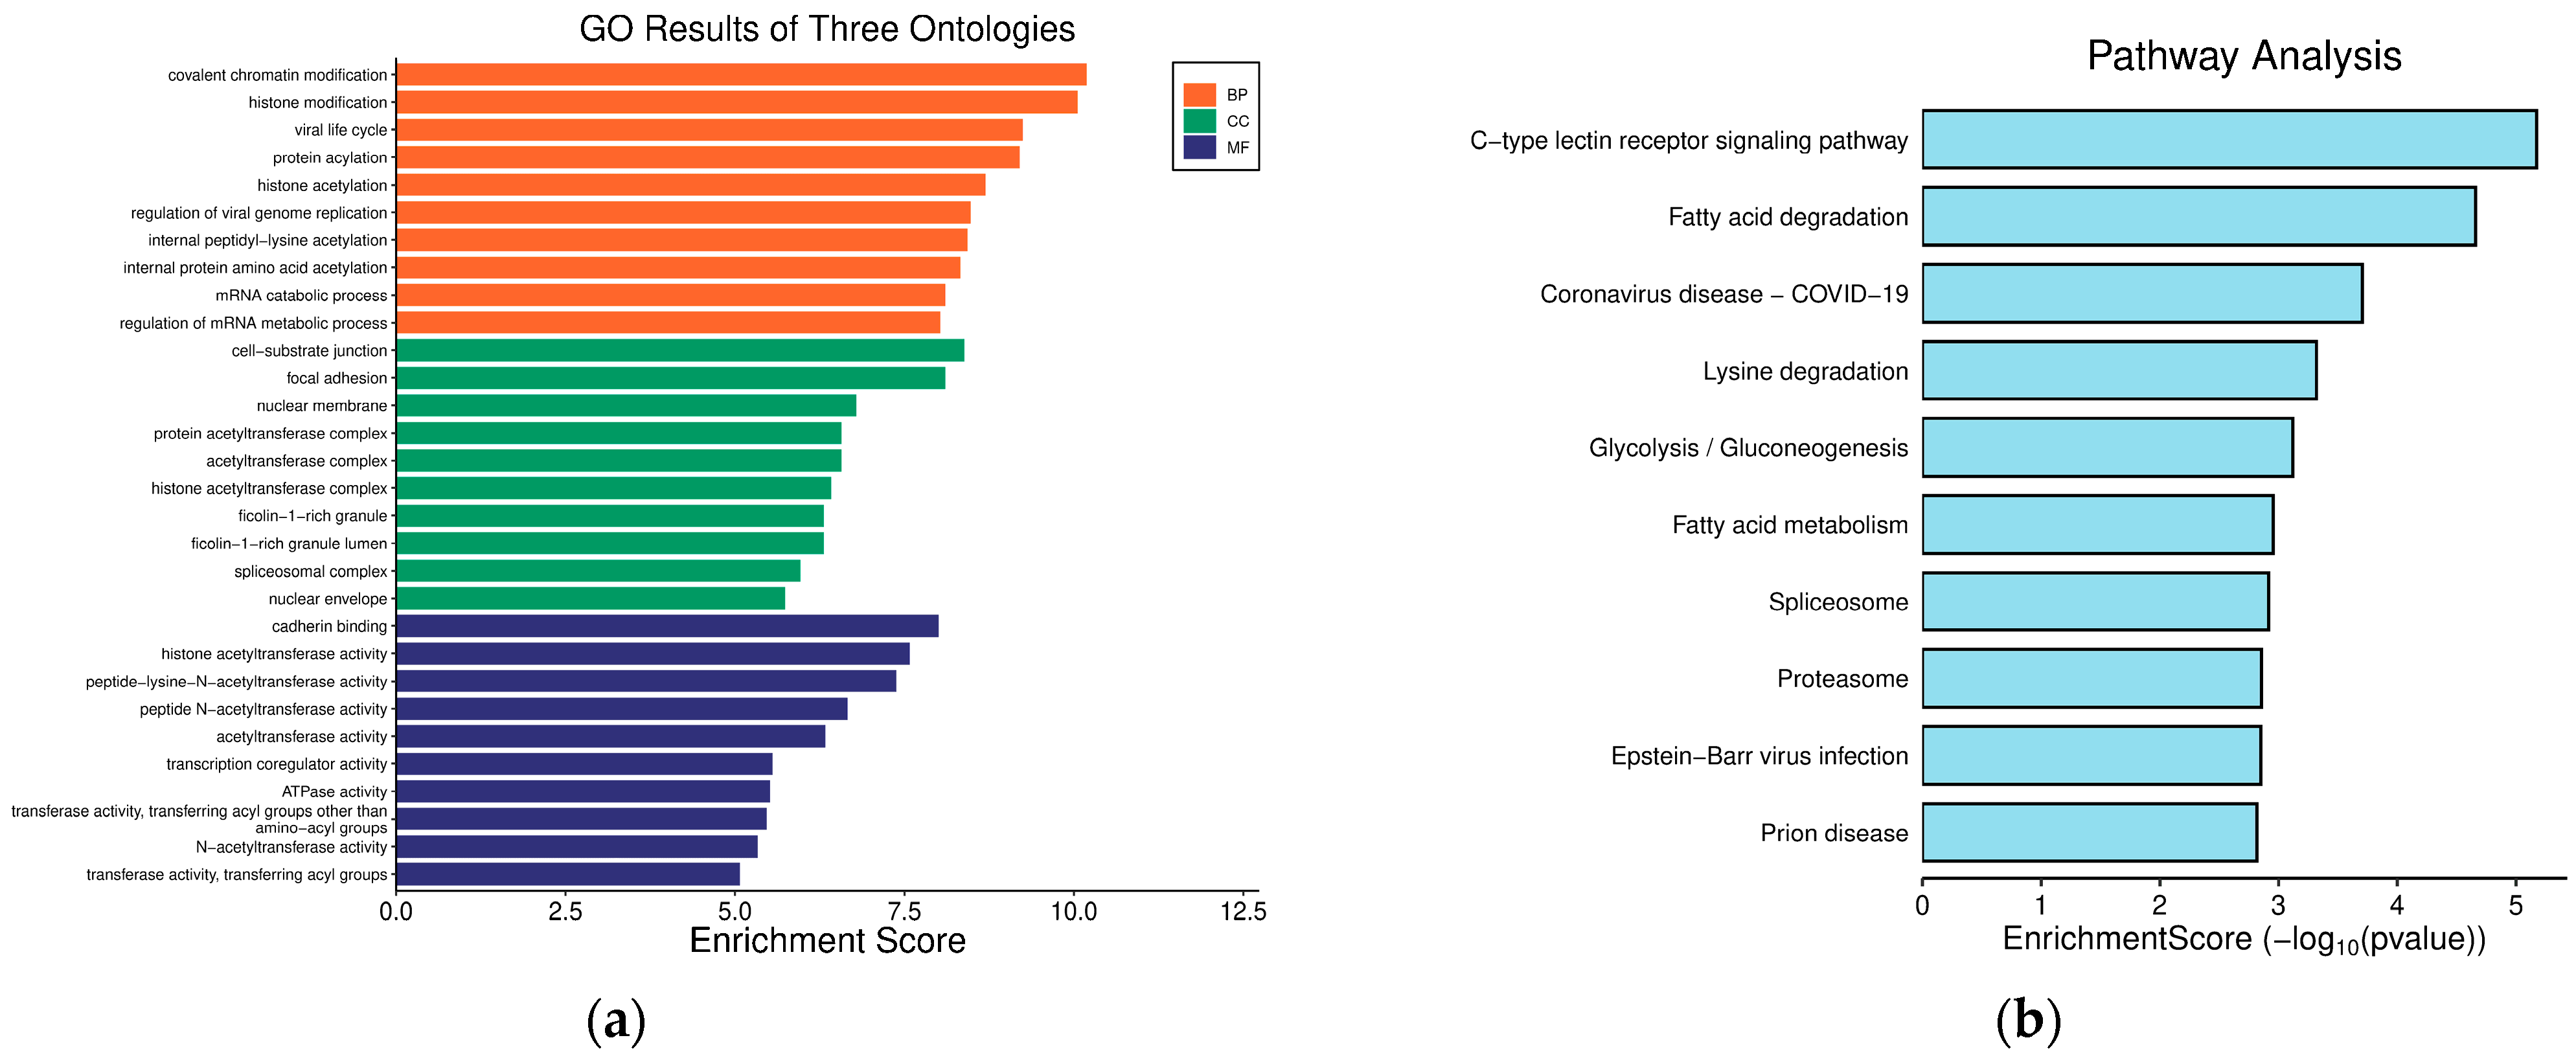

2.7. Functional Enrichment Analyses of Hub Genes

Functional enrichment analysis including GO and KEGG were performed to identify which DEGs were significantly enriched in GO terms and which metabolic pathways had a Bonferroni-corrected p-value ≤ 0.05 compared with the whole-transcriptome background. GO functional enrichment and KEGG pathway analysis were carried out by Goatools (version 0.12.1) and Python scipy (version 1.10.1) software, respectively.

Enrichment analyses, grouped by functional categories (

Table 3), revealed a predominance of RNA processing and immune response pathways consistent with

C. acnes-induced inflammation. These analyses further identified the C-type lectin receptor (CLR) signaling pathway as a key mediator of

C. acnes IA

1–induced inflammation. CLRs, expressed on keratinocytes and immune cells, recognize bacterial glycans, activating NF-κB and MAPK pathways to drive cytokine production [

25]. Our KEGG results, which also enriched NF-κB signaling, suggest a synergistic mechanism where

C. acnes IA

1 exploits CLR-mediated recognition to amplify inflammatory cascades, contributing to the chronicity of acne lesions [

26]. Additionally, enrichment of interferon-mediated signaling and Notch signaling indicates broader immune modulation, with interferons enhancing antiviral-like responses against bacterial PAMPs and Notch regulating epidermal differentiation [

27]. Reactome and Disease Ontology (DO) analyses further linked DEGs to chromatin modification and dermatological conditions, reinforcing acne’s inflammatory nature akin to psoriasis or eczema [

28].